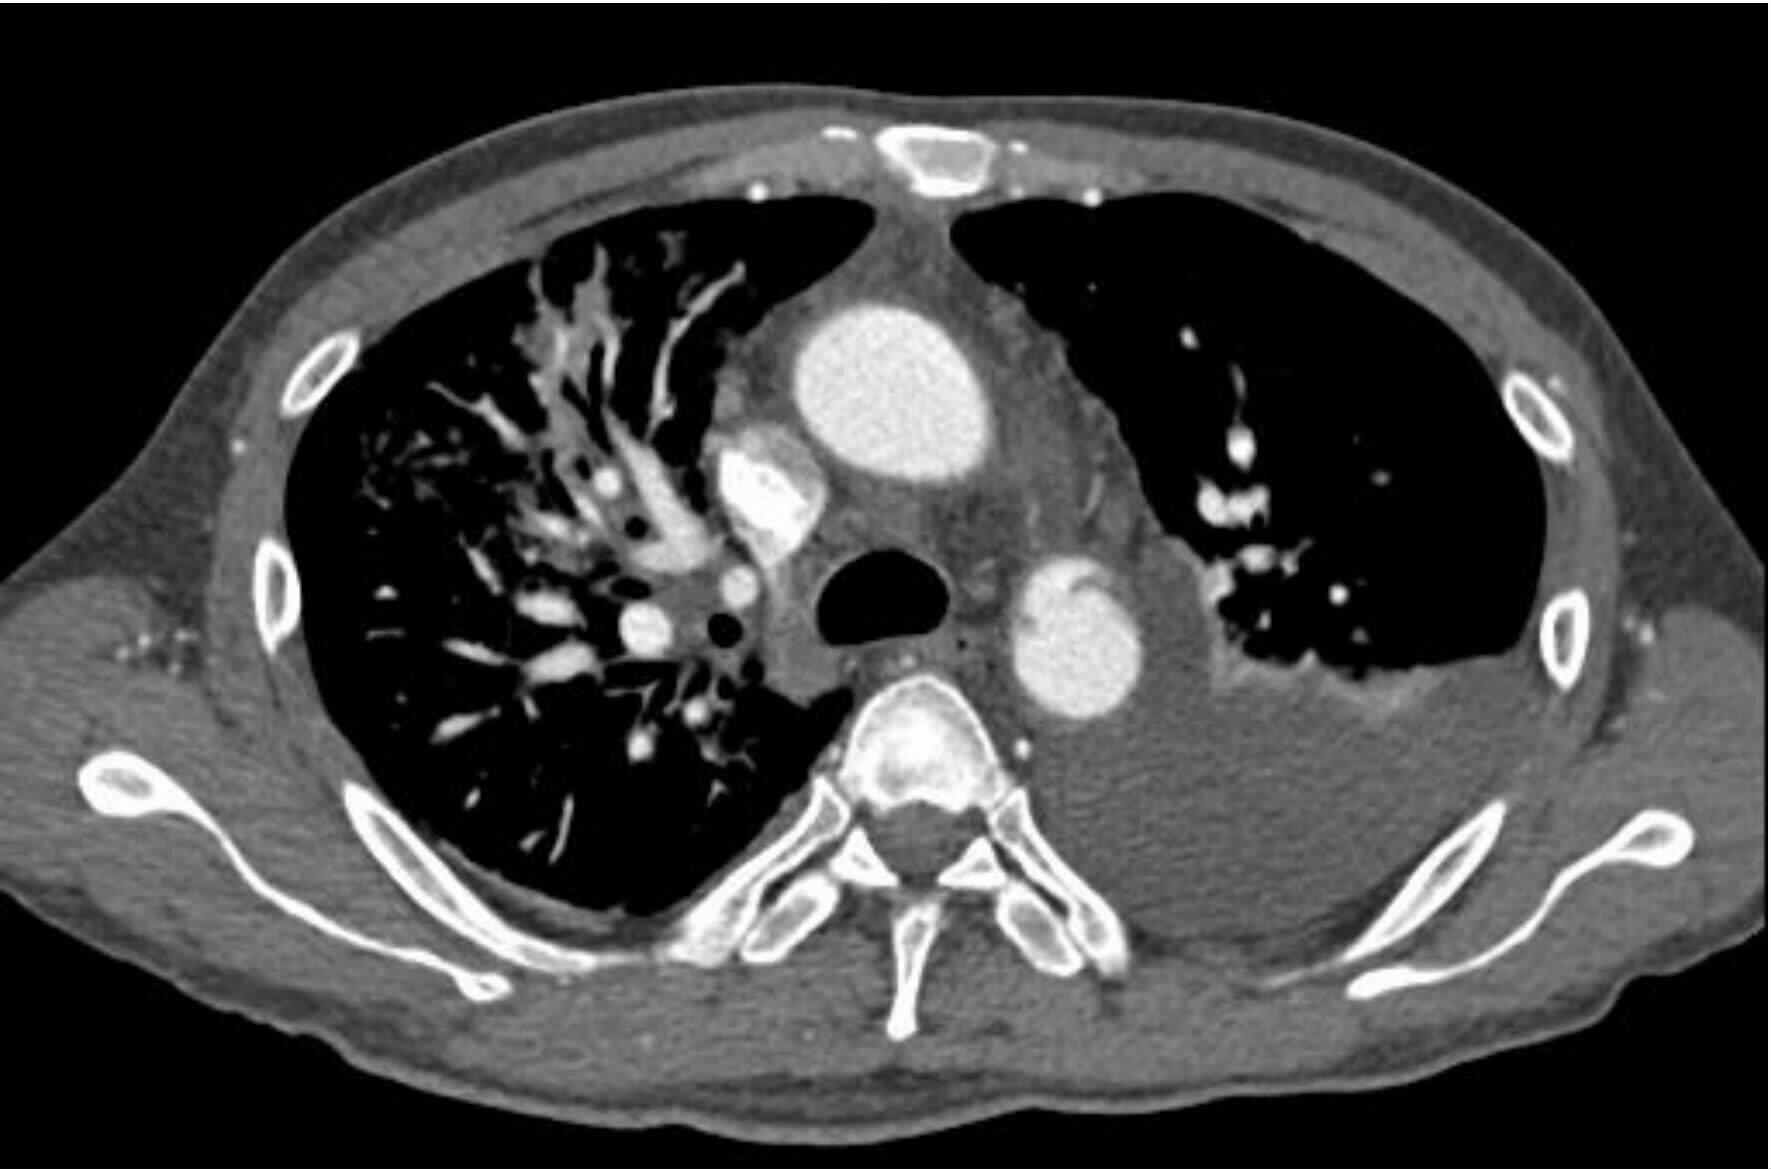

2 结果37例钝性胸主动脉损伤,CTA征象表现为内膜瓣、轮廓异常、血栓、动脉收缩、假性动脉瘤、主动脉夹层6种情况。①内膜瓣:内膜瓣为增强的主动脉管腔内可见一个或多个弧形弱化区(图 1)。②主动脉轮廓异常:表现为主动脉管壁或轮廓不规则,圆形的主动脉横切面发生变化,(图 2)。③假性动脉瘤:指主动脉壁破裂出血,形成主动脉壁外的血肿,主动脉管腔与不规则瘤腔结合处呈锐性边缘(单侧或双侧),(图 3)。④主动脉夹层:内膜片和主动脉真假两腔形成是诊断夹层动脉瘤的基本征象。内膜片将血管分为真假两个腔隙。增强早期真腔密度高于假腔,随时间延迟,假腔密度逐渐增高,假腔密度可等于或高于真腔,(图 4)。⑤动脉收缩表现为损伤节段主动动脉直径小于正常节段动脉直径(图 5)。⑥血栓;主动脉腔内息肉样低密度区(图 6)。本组37例钝性胸钝性胸主动脉损伤患者,CTA征象存在内膜瓣34例(91.8%),主动脉轮廓改变或腔异常37例(100%),动脉收缩17例(45.9%),主动脉夹层10例(27.0%),假性动脉瘤21例(56.7%),血栓1例(2.7%)。

| 图 2 主动脉峡部损伤动脉轮廓发生改变 Figure 2 Artery contour changes of aortic isthmus injury |